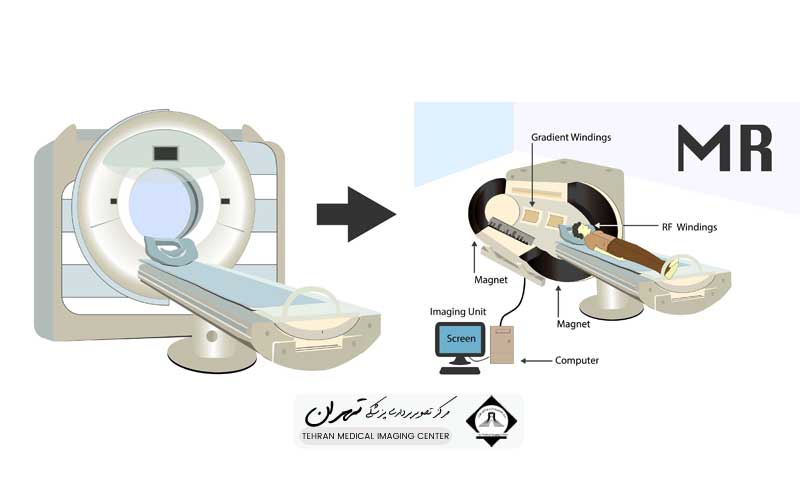

مهمترین فرق سی تی اسکن و ام آر آی در اصول فیزیکی و منابع انرژی است که برای تولید تصویر استفاده میکنند. سی تی اسکن که مخفف توموگرافی کامپیوتری است، از اشعه ایکس (X-Ray) استفاده میکند. در این روش، یک منبع اشعه ایکس حول بدن بیمار میچرخد و دهها هزار عکس از زوایای مختلف میگیرد.

پرتوهای اشعه ایکس از بافتهای مختلف بدن با درجات متفاوتی عبور میکنند؛ بافتهای متراکم مانند استخوانها پرتوها را بیشتر جذب میکنند و سفید به نظر میرسند، در حالی که بافتهای نرم و هوا اجازه عبور بیشتر پرتوها را میدهند. سپس، یک کامپیوتر پیشرفته این تصاویر مقطعی متعدد را جمعآوری کرده و یک تصویر سهبعدی و واضح از ساختارهای داخلی ایجاد میکند. این تکنیک به دلیل سرعت بالا و وضوح عالی در نمایش استخوانها شناخته میشود.

در مقابل، ام آر آی که مخفف تصویربرداری رزونانس مغناطیسی است، از میدانهای مغناطیسی بسیار قوی و امواج رادیویی (Radio waves) استفاده میکند. این میدان مغناطیسی، هستههای اتمهای هیدروژن موجود در مولکولهای آب بدن (که تقریباً در تمام بافتهای نرم به فراوانی یافت میشوند) را به یک جهت خاص همسو میکند.